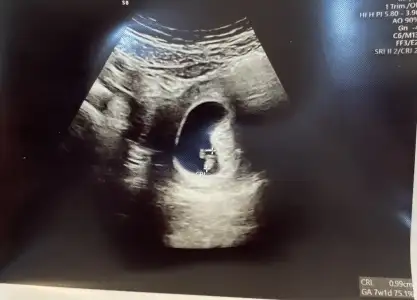

Kafam karıştı kızlar şimdi ilk attığım 5+2 vajinal ultrason, bugün ve şimdi yine attığım 7+1 karın ultrasonu tekrar bi bakıverin ayol ikisinde de aynı tarafta değil mi hiç anlamıyorum![]()

Evet bide o var işte normalde 11 Nisan sat yani bugün 9+0 olmalıydı ama 7+4 göründü bebek onu dert etmiyorum da kese bebeğe yetişirse biraz olsun rahatlayacam inşallahAynen yemin ederim mayıs ayı 3 yıl sürdü Haziran da şimdiden 3-5 ay gibi oldugeç döllenmeyse ileride toparlar oğlum geç döllenmeydi hep geriden geldi hatta çok geç dünyaya geldi ama maşallah sağlıklıydı senin de öyle olur inşallah

Keseyi gördüğünüz zaman kaç haftalıktı, kalp atışını gördüğünüzde kaç haftalıktı ve de programda yazıyordur ne zaman doğacağı onları soruyorŞehir mersin ama çok cahilim galiba diğer kese ve kalp atışından neyi kastettiniz hiç anlamadım11 hafta 1 günlük birde onu biliyorum uygulamadan